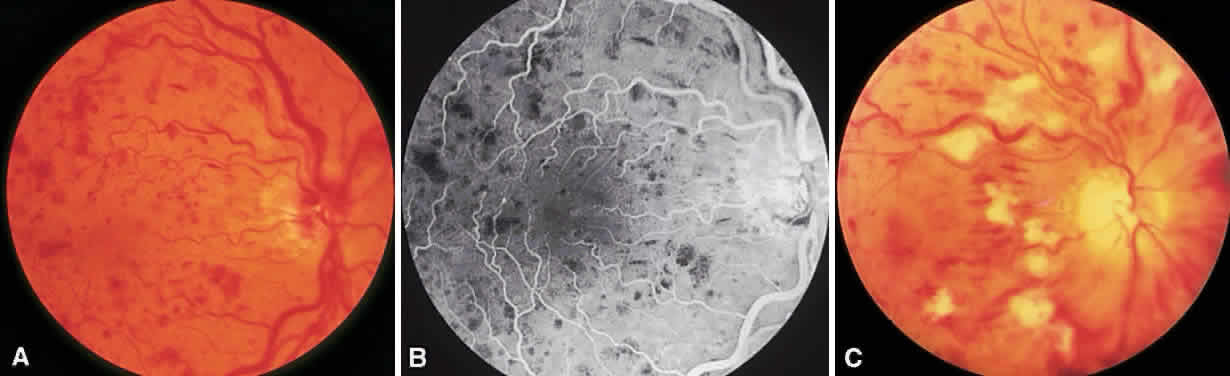

Central retinal vein occlusions (CRVOs) are caused by thrombosis formation within the vein at the level of the lamina cribrosa. Clinical findings in the setting of a CRVO include intraretinal hemorrhages in all four quadrants, increased dilation and tortuosity of the retinal veins, macular edema, nerve fiber layer infarcts, and disc edema. Acutely, the decrease in visual acuity is secondary to macular changes such as macular edema, hemorrhage and capillary nonperfusion. Long-term visual loss may be secondary to macular capillary nonperfusion, chronic macular edema, arteriole occlusion, tractional or exudative retinal detachment and neovascular glaucoma.48,49 Anterior segment neovascularization is much more common with CRVOs than BRVOs.

CRVOs are usually described as “ischemic” or “nonischemic” based on clinical examination and FA findings (Fig. 6). Roughly 75% to 80% of CRVOs are nonischemic. However, up to 34% of these will progress to the ischemic type usually within 1 year.46,47,50,51 An eye with a nonischemic CRVO typically has minimal capillary nonperfusion on FA, relatively few intraretinal hemorrhages, and a better visual prognosis than the ischemic variety. Ischemic CRVOs, conversely, have widespread capillary nonperfusion and are associated with a worse visual prognosis with increased risk of rubeosis iridis and neovascular glaucoma.52

Fig. 6. Nonischemic (A and B) and ischemic (C) central retinal vein occlusion.

The Central Vein Occlusion Study (CVOS) was a prospective, randomized, multicenter clinical trial designed to evaluate the role of PRP in promoting regression of anterior segment neovascularization resulting from ischemic CRVO, to determine the efficacy of macular grid laser photocoagulation for treating CRVO-related macular edema associated with visual acuity of 20/50 or worse, and to define the natural history of CRVO.53

The CVOS demonstrated that, although prophylactic PRP does decrease the risk of developing anterior segment neovascularization, prompt regression of neovascularization was more likely in eyes that had not received prior laser photocoagulation.54 Therefore, the study recommends observing ischemic CRVOs closely and treating with PRP at the first sign of iris or angle neovascularization rather than treating prophylactically. PRP may be warranted in the setting of acute ischemic CRVO if there is a high likelihood of poor patient compliance with follow-up. Unlike the BVOS, the CVOS did not demonstrate any benefit to laser photocoagulation for macular edema.55 Although laser therapy did decrease the amount of leakage on FA, there was no difference in visual acuity between treated and untreated eyes at any point in follow-up.